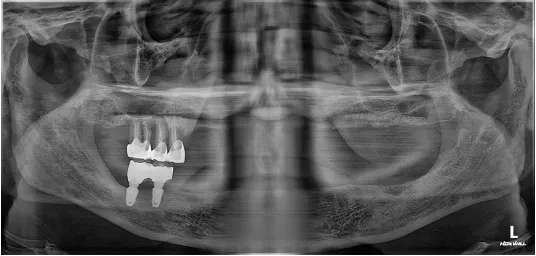

73세 고령의 남성환자분

지대치들이 파절되고 발치되어 내원하셨고 보철물 때문에 일상생활에 불편을 겪으셨습니다.

임플란트에 의한 재건을 원하셨으나, 골흡수가 심하고 하악구치부는 식립이 불가능하였습니다.

초진 X-RAY (2023.10.05)